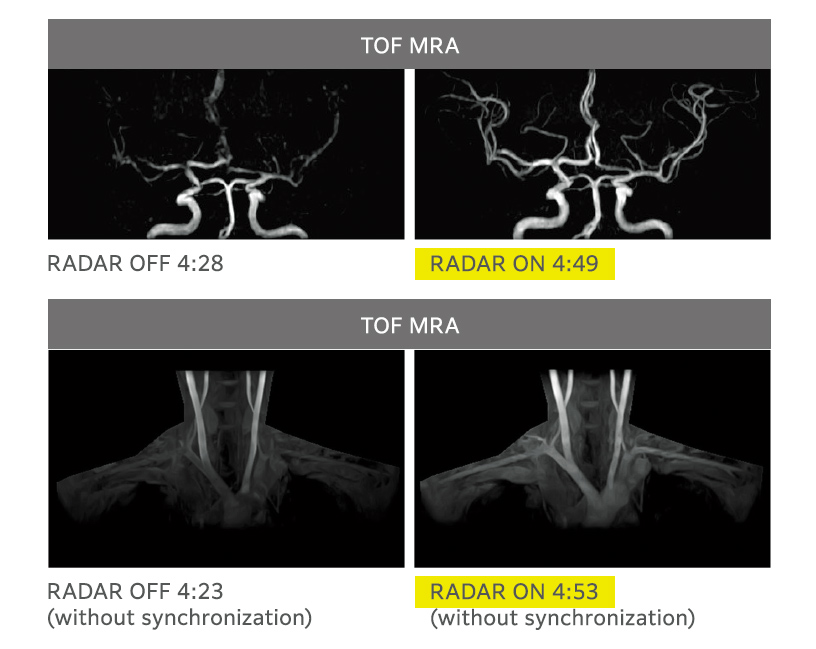

All Around RADAR

Rutin kafa incelemeleri için gerekli sekanslarda RADAR’ın kombine kullanımı

RADAR, birçok sekans, tüm alıcı bobinleri ve rastgele kesitlerle görüntüleme sırasında hareket artefaktlarını azaltarak kullanım kolaylığını artırır. RADAR, yüksek hızlı görüntüleme ile birlikte kullanılabilir. ECHELON Smart, TOF ve GrE sekanslarını destekler ve rutin baş incelemeleri için gerekli dizilerin çoğunda RADAR’ın kombine kullanımı ile uyumludur, böylece “All Around RADAR” özelliği gerçekleşir.

RADAR’ın TOF MRA ve GrE T2*WI’deki etkileri

RADAR, yüksek hassasiyetli sinyal düzeltme teknolojisi kullanılarak GrE sekanslarına uygulanmıştır. Bu, rutin baş incelemelerinde gerekli tüm sekanslar için RADAR’ın kombine kullanımını mümkün kılmıştır.